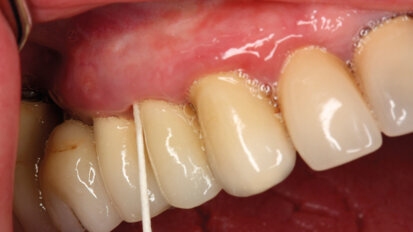

Modificazioni della flora microbica orale dopo attuazione di un piano di trattamento implanto-protesico

La riabilitazione orale mediante l’utilizzo di impianti osteointegrati in pazienti totalmente o parzialmente edentuli presenta un follow-up ...